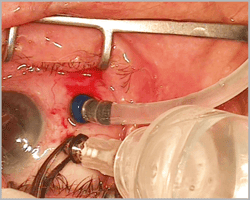

Akkan VFE Sistemi 20g ve 23g trokar sistemi ile kullanılır. VFE sistemi aspirasyon sırasında silikon yağının yayılmasını engeller. Göz içine girmeden silikonun aspirasyonunu sağlar.